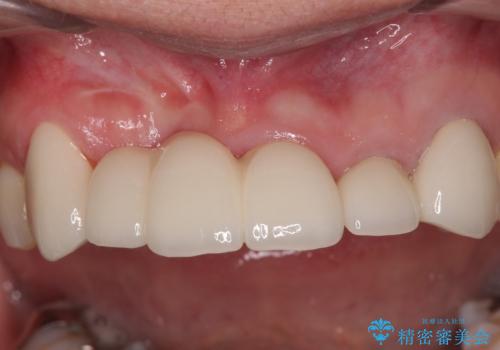

不具合の多い前歯 オールセラミックブリッジ治療

抜歯および根管治療を実施した後にオールセラミッククラウンにて補綴することとしました。

歯肉ラインの改善には歯周外科処置が必要でしたが、大きく笑っても歯肉ラインが唇に隠れるとのことで、外見の改善はせず、清掃性の大会ブリッジを装着いたしました。